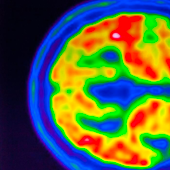

Los investigadores analizaron las medidas de presión arterial de 3.989 parejas estadounidenses, 1.086 parejas inglesas, 6.514 parejas chinas y 22.389 parejas indias, y descubrieron que la prevalencia de hipertensión en ambos cónyuges o parejas era del 47% en Inglaterra, el 38% en Estados Unidos, el 21% en China y el 20% en la India. En comparación con las mujeres casadas con maridos sin hipertensión, las mujeres cuyos maridos tenían hipertensión tenían un 9% más de probabilidades de padecerla en Estados Unidos e Inglaterra, un 19% más en la India y un 26% más en China.